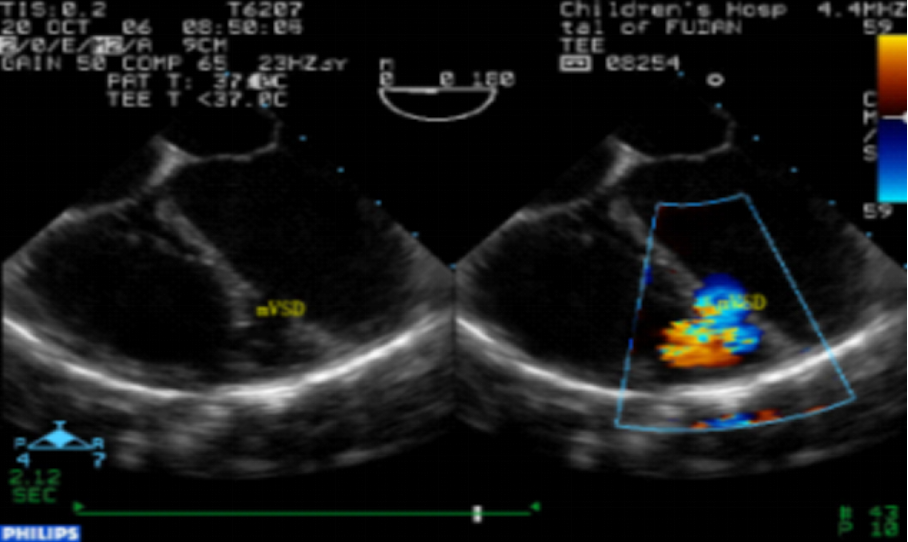

彩色超声心动图

二维及彩色多普勒显示肌部室间隔缺损